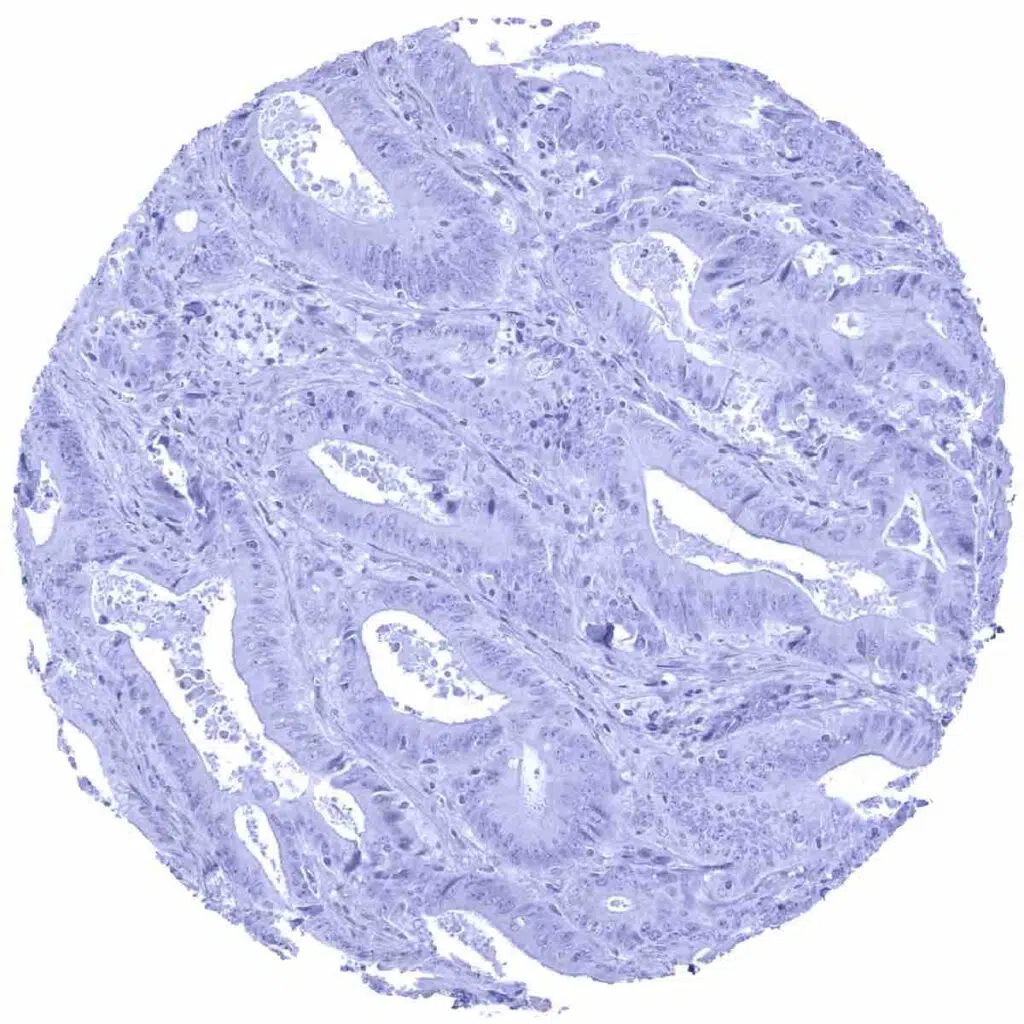

Larynx- Squamous cell carcinoma with intense Dsg1 immunostaining of tumor cells

Larynx- Squamous cell carcinoma with intense Dsg1 immunostaining of tumor cells. Staining is weaker at the periphery of tumor cell nests